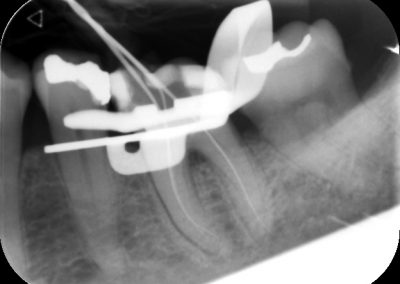

An access cavity is placed on the surface where the patient bites, to reach the root canals of the tooth. Once all the canals are identified, small files are used to remove the infected pulp.

Files of different sizes are used to eliminate bacteria and infection and to shape the canals. The canals are disinfected thoroughly with irrigants and later the canals will be sealed in 3 dimensions with a special medicament called gutta-percha to prevent reinfection of the tooth and the access cavity will be sealed with a temporary filling.